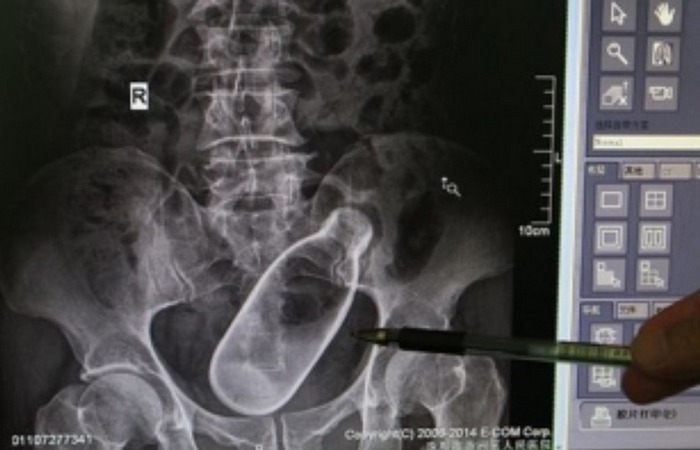

9 неожиданных предметов, которые врачи извлекли из пациентов

У Вас тут в бутылка...

Хирургов по праву можно считать настоящими волшебниками – они возвращают людей к жизни. Причём порой случается, что люди оказываются на операционном столе по весьма странным …